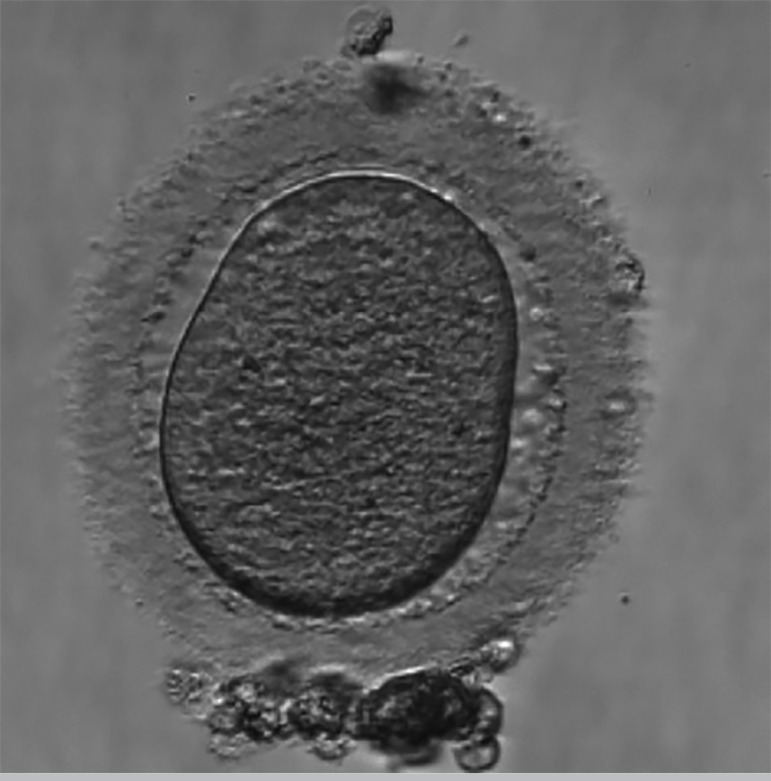

Oocyte quality could be negatively affected by many factors including smoking, alcohol consumption, obesity, woman's age, endometriosis and controlled ovarian stimulation (COS), during assisted reproductive technology (ART), in addition to genetic factors, such as hormone receptor polymorphisms, for example. We know that the increase in the reactive oxygen species (ROS) due to systemic disorders causes biochemical and morphological changes to the oocytes, interfering with their quality. The oocyte dysmorphism can be expressed through intra and/or extra cytoplasmic changes. In general, the size and number of oocytes' morphological abnormalities are directly related to preimplantation development failure. This case report is based on four in vitro fertilization (IVF) cycles performed by a patient with oocyte dysmorphism in all oocytes captured. The literature review on this topic aims to relate the characteristics of the oocytes, presented in the case report, with research results about the quality and morphology of the oocytes.